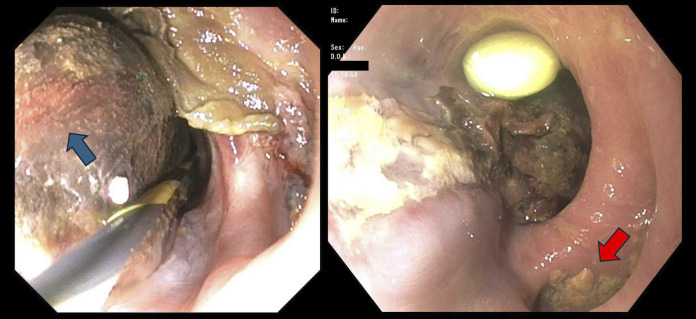

经食管超声心动图通常用于指导结构性心脏干预,但有食管损伤的风险。我们报告一位79岁的女性,她接受了经导管二尖瓣边缘修复术,并发食道血肿。急性胆囊炎并发难治性消化道出血及败血症。尽管采取了积极的措施,她还是没能活下来。我们的病例显示了经食管超声心动图相关并发症的潜在严重性,特别是在有食道憩室和抗凝使用等易感因素的患者中。

Transesophageal echocardiography is commonly used to guide structural cardiac interventions but carries a risk of esophageal injury. We present a 79-year-old woman who underwent a Transcatheter Edge-to-Edge Repair of the mitral valve and developed an esophageal hematoma. Clinical course was complicated by intractable gastrointestinal bleeding and sepsis due to acute cholecystitis. She did not survive despite aggressive measures. Our case demonstrates the potential severity of transesophageal echocardiography-related complications, especially in patients with predisposing factors such as esophageal diverticula and anticoagulation use.